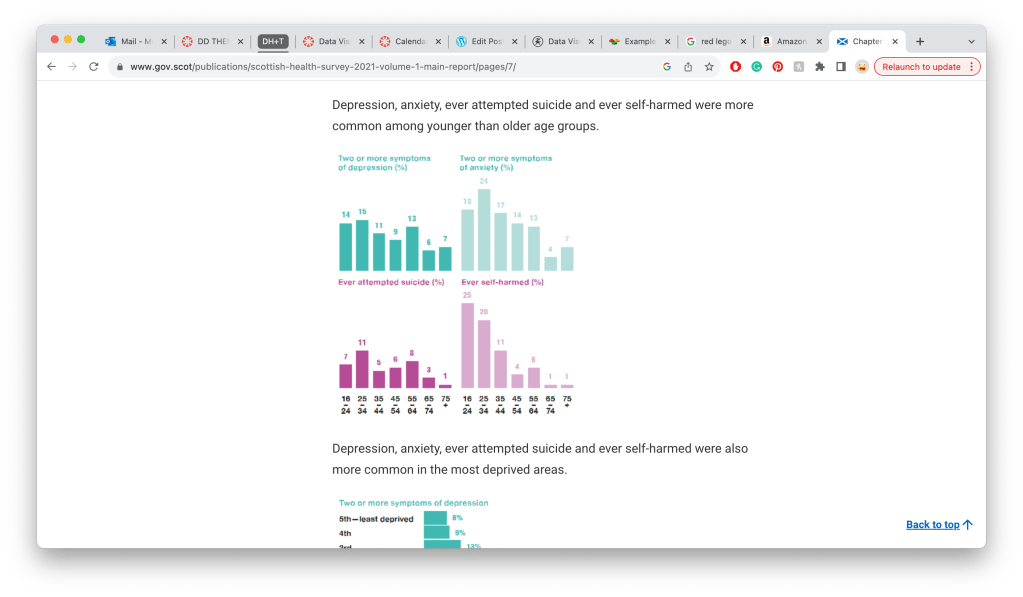

https://www.gov.scot/publications/scottish-health-survey-2021-volume-1-main-report/pages/7/